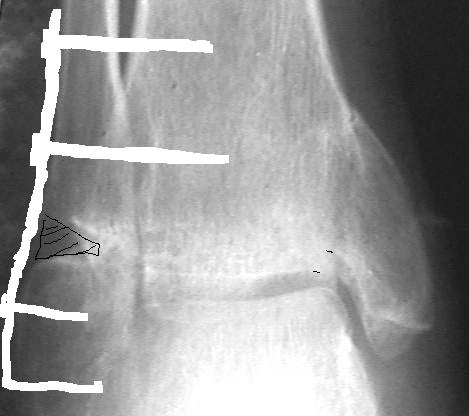

У больного травма в августе 2001 г. Лечился консервативно, Проводилась иммобилизация гипсовой лонгетой 3 мес. В последующем местное лечение. Остается контрактура боли в области наружной лодыжки. Направлен в наше отделение в конце января 2002 г Планируется костная аутопластика, остеосинтез пластиной, винтами перелома наружной лодыжки. Решается вопрос о коррекции неправильно сросшегося перелома внутренней лодыжки. Рентгенограммы: фас; профиль; план Сергей Зырянов

на снимке, кстати, срезан ее дистальный отдел, и правильность взаимоотношений с таранной костью не оценить. Если они правильные - я бы присоединился к мнению об оставлении ее покое.

А вот укорочение внутренней, похоже, привело к натяжению дельтовидной связки и гиперпрессии в медиальном отделе сустава, и уже сейчас там

видно сужение щели. Так что есть смысл обратить внимание на ортопедическую профилактику деформирующего артроза.